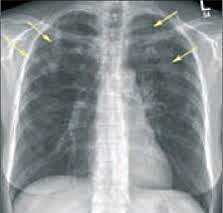

- Рентгенография легких. На снимках видны субплеврально расположенные одиночные (реже множественные, двусторонние) нечеткие затемнения средней интенсивности неправильной формы размером до 3-4 см. В окружении инфильтрата легочный рисунок усилен, тень корня легкого слегка расширена. Характерна быстрая динамика инфильтратов с миграцией по легочным полям и исчезновением не позднее 1-2 недель после обнаружения (чаще через 1-3 дня) без остаточной рубцовой деформации. При длительно поддерживающемся инфильтративном воспалении в ткани легких могут образоваться фиброзные очаги и кистозные полости.

- Рентгенография легких.Рентгенограммы при пневмонии обычно делают в начале заболевания и спустя 3-4 недели для контроля разрешения воспаления и исключения другой патологии (чаще бронхогенного рака легких). При любых видах пневмоний чаще процесс захватывает нижние доли легкого. На рентгенограммах при пневмонии могут выявляться следующие изменения: паренхиматозные (очаговые или диффузные затемнения различной локализации и протяженности); интерстициальные (легочный рисунок усилен за счет периваскулярной и перибронхиальной инфильтрации).

- Рентгенологические исследования. Одним из наиболее информативных методов диагностики легочных эозинофилий считается рентгенография грудной клетки. На снимках обнаруживаются летучие (мигрирующие) эозинофильные инфильтраты в виде участков затемнения. При аллергическом бронхолегочном аспергиллезе могут быть видны бронхоэктазы, фиброз верхних отделов легких.